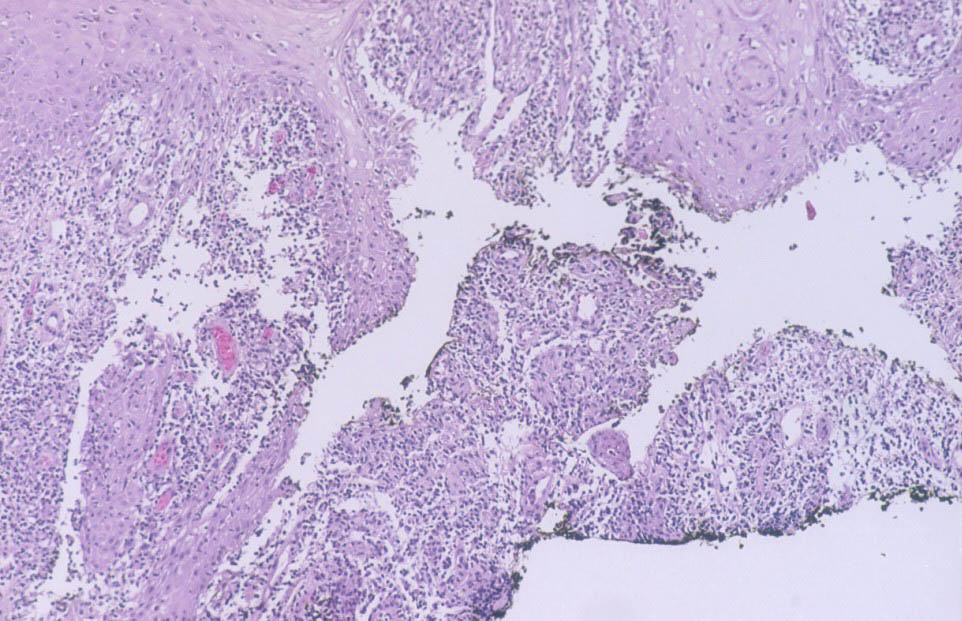

Histopathology.

Early lesions no more than 2 or 3 months old show a nonspecific inflammatory infiltrate composed of neutrophils, monocytes, and macrophages. In lesions about 4 months old, a few multinucleated giant cells and a few small epithelioid cell granulomas usually are present, and in lesions 6 months old or older, typical tubercles or tuberculoid structures may be seen (126). Areas of necrosis are only occasionally present in the centers of the granulomas. The epidermis often shows marked hyperkeratosis with an acute inflammatory infiltrate and ulceration .

Acid-fast bacilli usually can be identified in histologic sections of early lesions that show a nonspecific inflammatory infiltrate. In contrast, tuberculoid granulomas generally no longer show acid-fast organisms unless areas of central necrosis are present. Although primary lesions usually require a few months for the formation of tuberculoid granulomas, the sporotrichoid nodules that arise later show tuberculoid granulomas and a lack of acid­fast bacilli even when they have been present for only a few weeks.